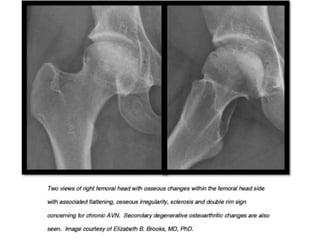

Jaccoud’s-like arthropathy.

These hand deformities resemble those that develop in patients with a history of rheumatic

fever and are caused by ligamentous and/or joint capsule laxity.

Deformities in the hands, such as ulnar drift at the metacarpophalangeal joints, swan neck

and boutonnière deformities, and hyperextension at the interphalangeal joint of the thumb,

closely resemble the deformities seen in rheumatoid arthritis.

Absence of erosions on radiographs and their reducibility distinguish this condition from the

deforming arthritis of rheumatoid arthritis.

Jaccoud’s-like arthropathy. These handdeformities resemble those that develop in patients with a history of rheumatic fever and are caused by ligamentous and/or joint capsule laxity. Deformities in the hands, such as ulnar drift at the metacarpophalangeal joints, swan neck and boutonnière deformities, and hyperextension at the interphalangeal joint of the thumb, closely resemble the deformities seen in rheumatoid arthritis. Absence of erosions on radiographs and their reducibility distinguish this condition from the deforming arthritis of rheumatoid arthritis.